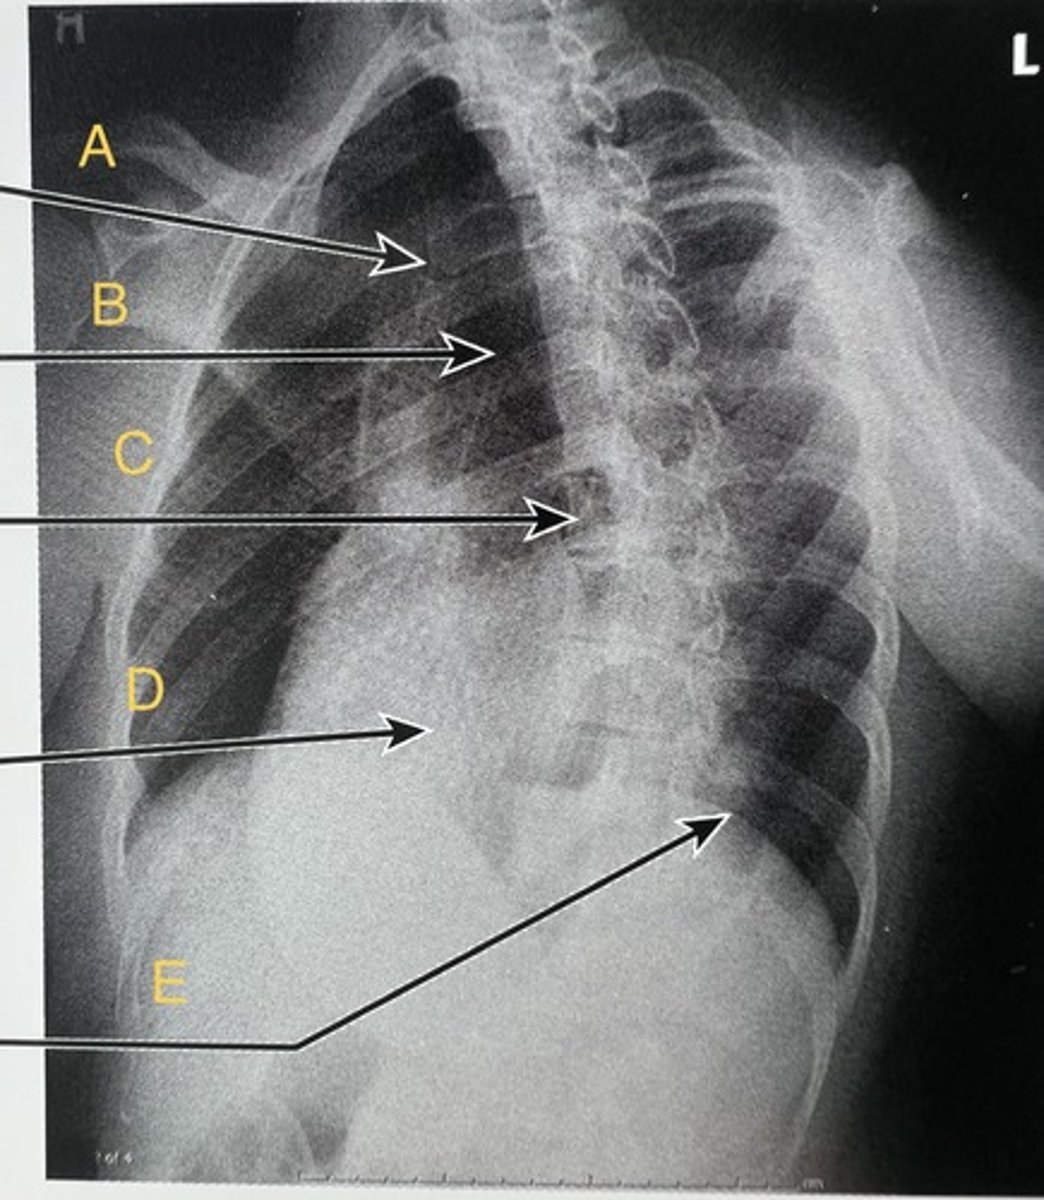

T3 body

A.

T7 body

B.

T11-12 intervertebral foramen

C.

Lateral T-spine

What position?